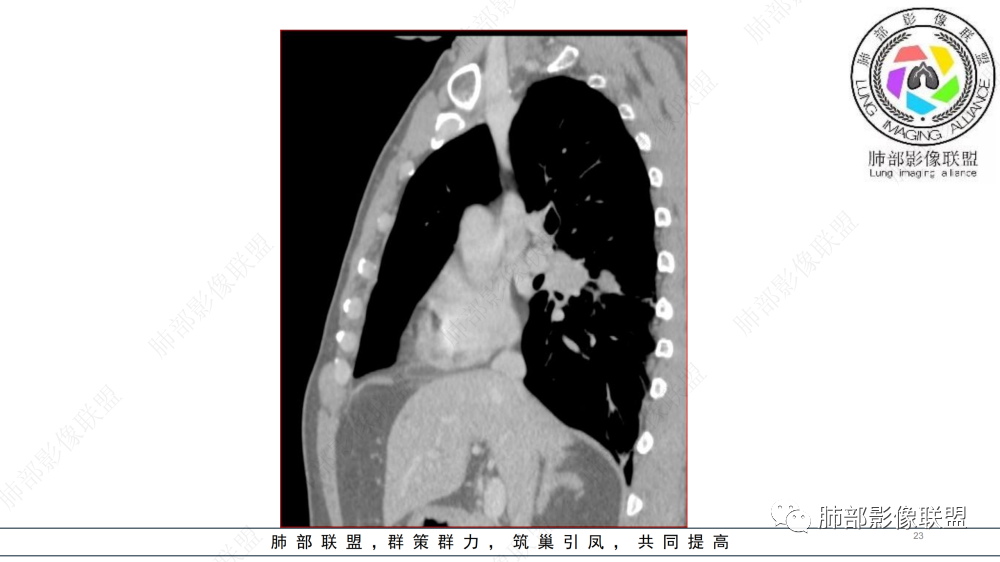

晨读 右肺中间段支气管至下叶支气管狹窄,腔内见软组织肿块,腔内外侵犯,右下肺门软组织肿块形成,不均匀强化,冠状位病变纵径大于横径,远侧肺内阻塞性炎症。定性恶性,考虑腺样囊腺癌或鳞癌

右肺下叶肺门区肿块,向中间段支气管突出,下叶支气管阻塞狭窄,腔内外侵犯,不均匀强化,内可见低密度,冠状位病变沿支气管走行生长,远侧肺内阻塞性炎症,考虑鳞癌,鉴别类癌

中老年男性,右肺下叶背段支气管内新生物,近端可见息肉样突起,远端沿分支支气管生长堵塞,肺门口病灶增强后明显强化,峰值达140hu,远端部分强化不明显考虑粘液栓,考虑典型类癌,鉴别鳞癌。

右肺叶中间段支气管见软组织影不完全阻塞及管腔变窄,向管腔外突破,向下叶背段浸润性生长,见指套及息肉样特点,不均匀明显强化,右肺下叶背段少许阻塞性炎症,肯定恶性肿瘤,小细胞Ca首先,支气管疾病谱恶性肿瘤:类癌,鳞癌,囊腺癌,粘液表皮样癌,与鳞癌,囊腺癌鉴别,支气管镜取材活检可以明确诊断。

晨读:男,57,咳嗽半年,痰中带血3天。胸部CT:右中间段支气管到下叶支气管堵塞性狭窄,管腔内见软组织肿块,壁内外侵犯,长轴沿气道延展,下叶基底多段累及,病变纵径大于横径,远侧可见索条、阻塞性炎症。考虑恶性,腺样囊腺癌?鳞?鉴别N内分泌类、炎性肉芽肿等